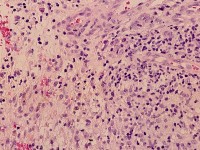

![Buruli ulcus (click on photo to enlarge) [source: www.huidziekten.nl] Buruli ulcus](../../../images/Buruli-ulcus-5z.jpg) |

![Buruli ulcus (click on photo to enlarge) [source: www.huidziekten.nl] Buruli ulcus](../../../images/Buruli-ulcus-6z.jpg) |

| HE kleuring |

Ziehl

Neelsen kleuring |